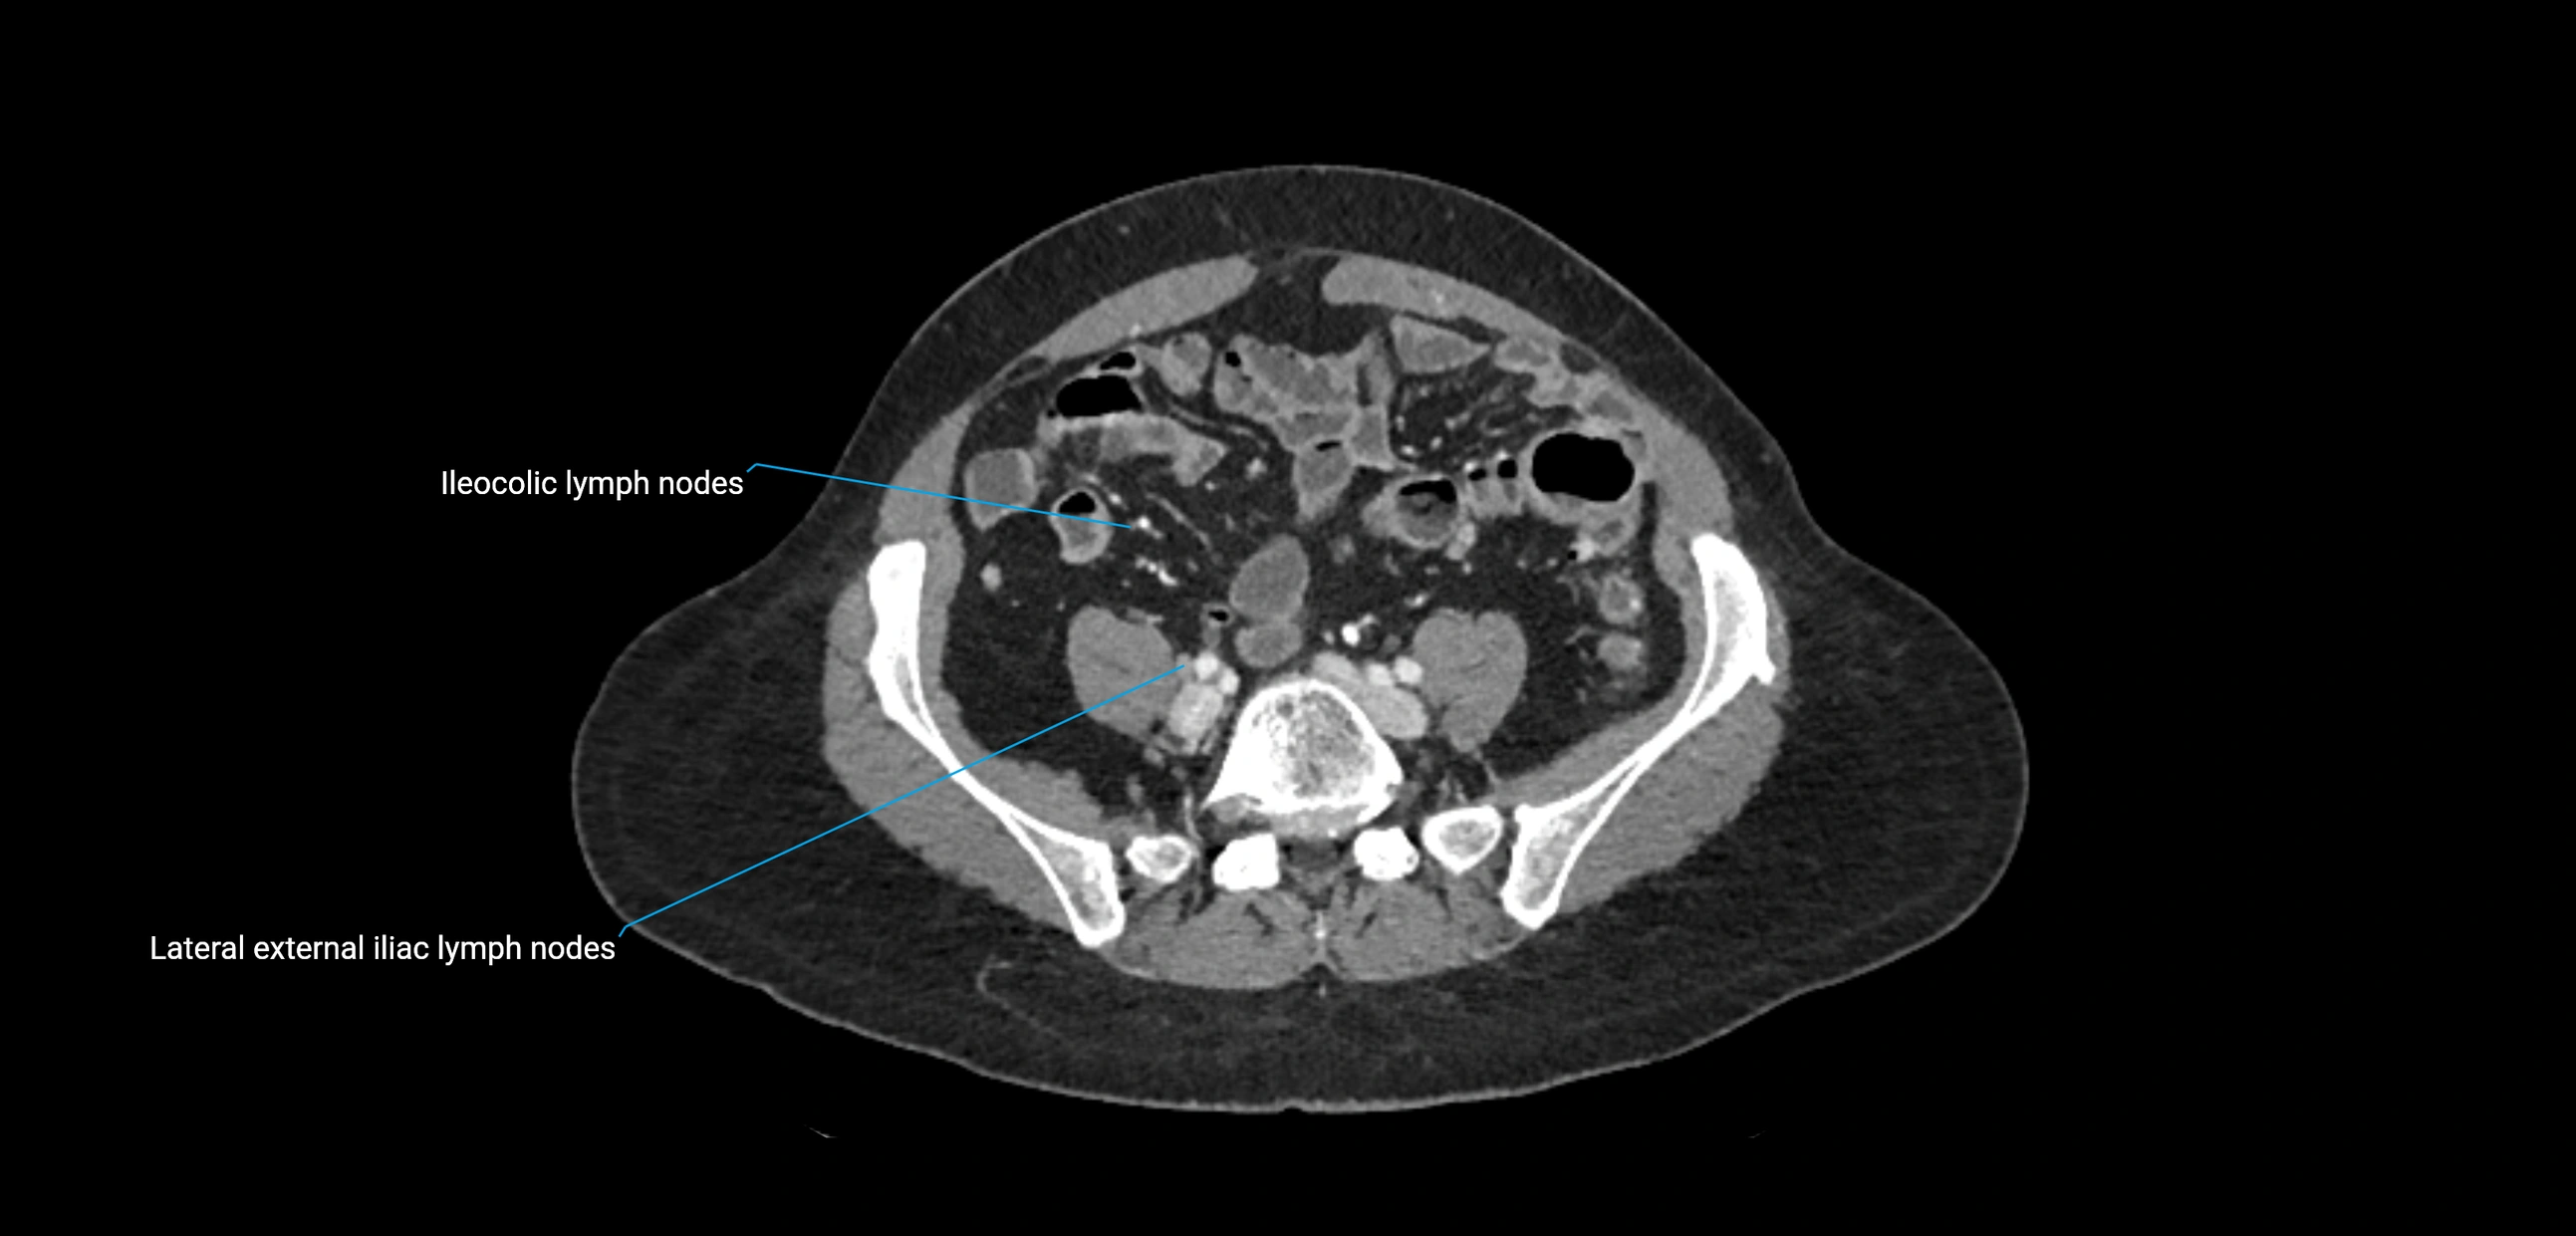

MRI images

image